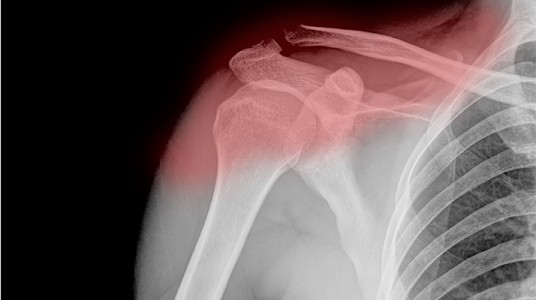

معروف طبياً أن المفصل الطبيعي للكتف يتكون من التقاء عظمتي لوح الكتف والساعد.

وهناك أجزاء عظمية تغلفها طبقات من الأنسجة الرخوة المهمة كالأربطة والعضلات والأوتار التي تلتف حول أجزاء المفصل من الأمام والخلف ومن الجانب لتوفر لهذا المفصل المهم مرونته وثباته وقوته.

إلا أن هذه التركيبة المعقدة، كما يقول استشاري العظام والمفاصل وجراحة العمود الفقري د. ياسر البحيري، تجعل هذه الأنسجة الرخوة المعروفة باسم (Rotator cuff) عرضة للالتهابات غير الجرثومية (inflammation) نتيجة للتقدم في السن أو نتيجة الإجهاد المزمن أو الإصابات المباشرة لمنطقة الكتف كما يحصل عند الرياضيين التي قد تؤدي إلى قطع تام في هذه الأوتار (Rotator cuff tear).

أما التشخيص فعادة ما يكون بعد الفحص السريري الذي يبين وجود ضمور في عضلات الكتف وبروز في العظام وآلام عند تحريك الكتف وصعوبة في رفع الذراع للأمام.

كما أن أشعة الرنين المغناطيسي هي الأفضل والأمثل في إظهار الأوتار المريضة ومدى شدة المرض ومكانه ووجود قطع الوتر من عدمه.